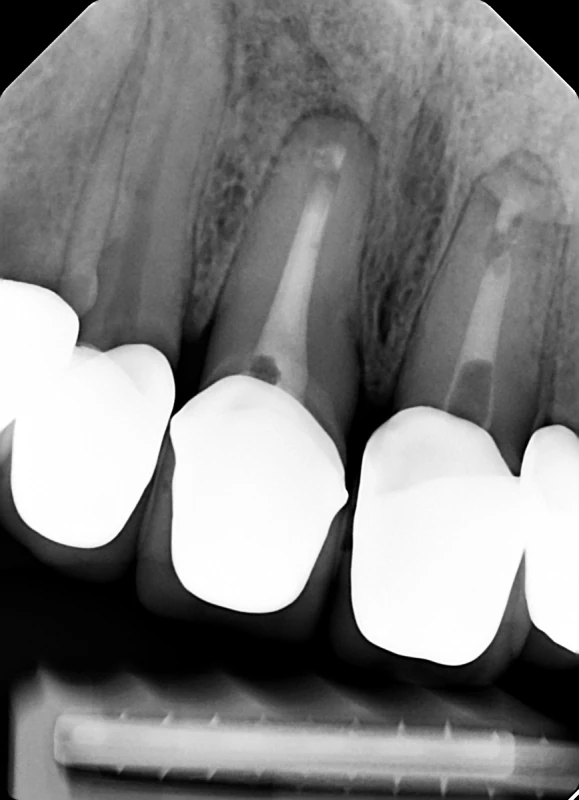

Die Wurzelspitzenresektion (WSR) ist ein operativer Eingriff, der bei entzündeten Wurzelspitzen eines Zahnes durchgeführt wird. Dabei wird das entzündete Gewebe an der Wurzelspitze sowie ein Teil der Zahnwurzel entfernt. Dieser Eingriff ist erforderlich, wenn eine herkömmliche Wurzelkanalbehandlung nicht ausreicht. Die WSR wird unter örtlicher Betäubung vom Zahnarzt durchgeführt und wird in der Regel von der gesetzlichen Krankenkasse übernommen.

Eine Wurzelspitzenresektion, auch bekannt als WSR, ist ein operativer Eingriff, der häufig bei entzündeten Wurzelspitzen eines Zahns durchgeführt wird. Wenn eine herkömmliche Wurzelkanalbehandlung nicht ausreicht, um die Entzündung zu behandeln, kann eine WSR erforderlich sein. Dabei wird das entzündete Gewebe an der Wurzelspitze und ein Teil der Zahnwurzel entfernt. Der Eingriff wird unter örtlicher Betäubung durchgeführt und dient dazu, Schmerzen zu lindern und den betroffenen Zahn zu erhalten. In vielen Fällen übernimmt die gesetzliche Krankenkasse die Kosten für die Behandlung.

Eine Wurzelspitzenresektion wird in der Regel durchgeführt, wenn eine Entzündung an der Wurzelspitze eines Zahnes vorliegt, die durch eine herkömmliche Wurzelkanalbehandlung nicht erfolgreich behandelt werden kann. Oftmals ist auch eine erneute Entzündung nach einer bereits durchgeführten Wurzelbehandlung der Grund für den Eingriff. In manchen Fällen kann eine Wurzelspitzenresektion erforderlich sein, um einen Zahn zu erhalten und den betroffenen Patienten vor weiteren Schmerzen zu bewahren. Dabei wird das entzündete Gewebe an der Wurzelspitze entfernt und gegebenenfalls auch ein Teil der Zahnwurzel und des umliegenden Knochens. Der Eingriff wird in der Regel unter örtlicher Betäubung durchgeführt und kann oft eine Alternative zur Entfernung des gesamten Zahnes darstellen.

Im Gegensatz dazu wird bei einer Wurzelspitzenresektion der entzündete Bereich an der Spitze der Zahnwurzel chirurgisch entfernt. Dieser Eingriff wird häufig durchgeführt, wenn eine Wurzelkanalbehandlung nicht erfolgreich war oder die Infektion sich bis zur Wurzelspitze ausgebreitet hat.

Eine Wurzelspitzenresektion ist ein chirurgischer Eingriff, der durchgeführt wird, wenn eine Wurzelkanalbehandlung nicht ausreicht, um eine Entzündung im Zahn zu beseitigen. Der Eingriff erfolgt unter örtlicher Betäubung und beginnt mit einem kleinen Schnitt im Zahnfleisch, um Zugang zur Wurzelspitze zu erhalten. Anschließend wird die entzündete Spitze der Wurzel entfernt und der Wurzelkanal gereinigt und desinfiziert. Nach der Reinigung wird der Wurzelkanal mit einer Füllung verschlossen, um eine erneute Entzündung zu verhindern. Die Wunde im Zahnfleisch wird dann mit feinen Nähten verschlossen. Die Heilung nach einer Wurzelspitzenresektion verläuft in der Regel komplikationslos, jedoch kann es zu leichten Schwellungen und Schmerzen kommen, die mit Schmerzmitteln behandelt werden können.